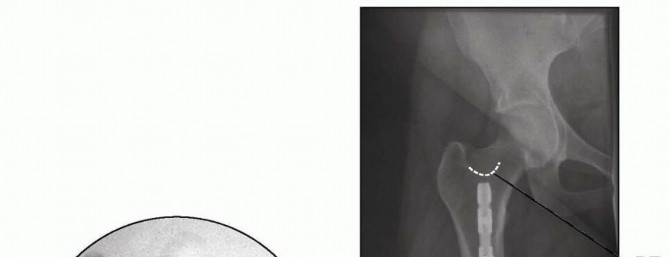

Once the fracture is reduced on the AP and lateral images, the surgeon passes the guidewire to end just below the level of the piriformis fossa. This is done to ensure that reaming is performed past the level of the lesser trochanter because the reamers stop at the beaded portion of the guidewire. 5. ## Reaming Reaming should begin with an end-cutting reamer (typically size 8 mm or 9 mm in diameter). Fracture reduction must be maintained throughout the reaming process to minimize eccentric reaming. Reaming should be performed slowly and in 0.5-mm increments to prevent thermal necrosis. The approximate nail diameter is selected based on the preoperative measurement of the femoral isthmus. The final nail diameter should be selected based on the size of the reamer that provides the initial cortical chatter. The canal is reamed to 1.0 to 1.5 mm over the selected nail diameter. Nail length can be determined multiple ways: A radiolucent ruler can be placed on the anterior aspect of the femur. The nail should end above the level of the lesser trochanter on the AP radiograph and should be measured so that it is deep to the apex of the line of Blumensaat on the lateral view (see FIG 1C).  --- TECH FIG 1 • Schematic diagram of a lateral view of the knee, obtaining femoral length measurement using the twoguidewire technique. The amount of guidewire B (asterisk) indicated by the bracket equals the amount of guidewire A in the femoral canal. Alternatively, a second guidewire of the same length can be inserted into the knee to end just deep to the apex of the line of Blumensaat on the lateral fluoroscopic image. This additional guidewire is clamped at the level of the guidewire already in place. The portion distal to the guidewire in place is measured to equal the amount of guidewire in the femoral canal ( TECH FIG 1). In addition, many nailing systems have system-specific measurement guides that are outlined in their technique manuals. If the measurement is between nail sizes, the shorter nail is selected. Length can be added with an end cap if required. 6. ## Placing the Nail Once the nail size is selected, the nail is inserted over the guidewire. Most current systems allow the beaded-tip guidewire to pass through the cannulated nail. If an older system is being used, then the beaded-tip guidewire must be exchanged for a smoothtip guidewire using an exchange tube. If guidewire exchange is required, the surgeon ensures correct placement of the smooth-tip guidewire on the AP and lateral images before nail insertion. The nail is inserted over the guidewire and should pass relatively easily. If the nail does not advance easily, the surgeon performs a careful AP and lateral fluoroscopic assessment of the fracture reduction and nail placement. Nail insertion depth is assessed on the lateral knee radiograph. The nail should end proximal to the apex of the line of Blumensaat to ensure subchondral placement ( TECH FIG 2A). The surgeon confirms that fracture length and alignment have been restored on the AP and lateral radiographs. The surgeon confirms that the nail length selected puts the proximal tip of the nail ending at or above the level of the lesser trochanter ( TECH FIG 2B). The nail is advanced if the proximal tip does not end at or above the level of the lesser trochanter. If this leaves the nail countersunk, end caps can be selected to gain nail length. Care must be taken to remain below the piriformis fossa to avoid proximal nail protrusion. The nail is locked distally using the distal interlocking guides. We typically use one lateral to medial distal interlocking screw for transverse midshaft femoral fractures, and a second anterolateral to posteromedial distal interlocking screw for comminuted or distal femoral fractures. Using live fluoroscopy, the fluoroscopic machine is rotated about the knee to assess the length of the interlocking

--- TECH FIG 1 • Schematic diagram of a lateral view of the knee, obtaining femoral length measurement using the twoguidewire technique. The amount of guidewire B (asterisk) indicated by the bracket equals the amount of guidewire A in the femoral canal. Alternatively, a second guidewire of the same length can be inserted into the knee to end just deep to the apex of the line of Blumensaat on the lateral fluoroscopic image. This additional guidewire is clamped at the level of the guidewire already in place. The portion distal to the guidewire in place is measured to equal the amount of guidewire in the femoral canal ( TECH FIG 1). In addition, many nailing systems have system-specific measurement guides that are outlined in their technique manuals. If the measurement is between nail sizes, the shorter nail is selected. Length can be added with an end cap if required. 6. ## Placing the Nail Once the nail size is selected, the nail is inserted over the guidewire. Most current systems allow the beaded-tip guidewire to pass through the cannulated nail. If an older system is being used, then the beaded-tip guidewire must be exchanged for a smoothtip guidewire using an exchange tube. If guidewire exchange is required, the surgeon ensures correct placement of the smooth-tip guidewire on the AP and lateral images before nail insertion. The nail is inserted over the guidewire and should pass relatively easily. If the nail does not advance easily, the surgeon performs a careful AP and lateral fluoroscopic assessment of the fracture reduction and nail placement. Nail insertion depth is assessed on the lateral knee radiograph. The nail should end proximal to the apex of the line of Blumensaat to ensure subchondral placement ( TECH FIG 2A). The surgeon confirms that fracture length and alignment have been restored on the AP and lateral radiographs. The surgeon confirms that the nail length selected puts the proximal tip of the nail ending at or above the level of the lesser trochanter ( TECH FIG 2B). The nail is advanced if the proximal tip does not end at or above the level of the lesser trochanter. If this leaves the nail countersunk, end caps can be selected to gain nail length. Care must be taken to remain below the piriformis fossa to avoid proximal nail protrusion. The nail is locked distally using the distal interlocking guides. We typically use one lateral to medial distal interlocking screw for transverse midshaft femoral fractures, and a second anterolateral to posteromedial distal interlocking screw for comminuted or distal femoral fractures. Using live fluoroscopy, the fluoroscopic machine is rotated about the knee to assess the length of the interlocking

---  TECH FIG 2 • A. Postoperative lateral radiograph of the knee, showing correct retrograde femoral nail insertion depth deep to the line of Blumensaat (BL). B. Postoperative AP radiograph of the hip, showing correct retrograde femoral nail insertion depth above the lesser trochanter of the femur but below the radiographic landmark for the piriformis fossa (PF). The surgeon should consider using washers, a medial locking nut, or a locking end cap (which locks the most distal interlocking screw to the nail) as options for osteoporotic bone. Once distal interlocking screw fixation is complete, the surgeon reassesses the fracture reduction fluoroscopically. If any shortening has occurred, length can be regained by manual traction or by backslapping the nail with the insertion guide nail removal attachment (the surgeon must exercise caution when using this technique in patients with osteoporotic bone). 7. ## Screw Fixation Proximal interlocking screw fixation is performed in the anterior to posterior plane using the freehand perfect circle technique. 7 First, a magnified AP image of the proximal femur is obtained. The fluoroscopy machine is rotated until the proximal interlocking hole is seen as a “perfect circle” (also discussed in Chap. 44, Antegrade Intramedullary Nailing of the Femur; Tech Fig 4, Distal interlocking screw placement). A 1-cm incision is made in the proximal aspect of the thigh, anteriorly centered over the proximal interlocking hole, as visualized on the AP radiograph. Careful blunt dissection exposes the anterior femur. The proximal femur's dense cortical bone makes it difficult to start a hole using a standard drill bit. The pointed soft tissue guides from large external fixation systems or a pointed drill bit can be used to prevent slipping off of the anterior cortex. The femoral artery lies 1 cm medial to the femur at the level of the lesser trochanter, so the surgeon must avoid slipping off the femur medially. Once the drill passes through the first cortex, it is removed from the drill bit to confirm radiographically that it will pass though the nail by the appearance of a perfect circle within the proximal interlocking hole. Small changes in the drill angle can be made to ensure correct passage through the interlocking hole. With a mallet, the drill bit can be gently tapped through the nail hole. The drill is then reattached to complete drilling through the posterior aspect of the proximal femur. Because of the proximity of the sciatic nerve, care should be taken to ensure that the drill is not advanced too far past the posterior cortex. Before removing the drill, the surgeon must reconfirm correct rotational alignment by flexing the hip and knee and assessing the hip's internal and external rotation profile. It is compared with the normal internal and external rotation of the contralateral uninjured hip that was examined preoperatively. Screw length measurement can be confirmed with a frog-leg lateral or a true lateral view with flexing of the hip to clear the contralateral leg.

TECH FIG 2 • A. Postoperative lateral radiograph of the knee, showing correct retrograde femoral nail insertion depth deep to the line of Blumensaat (BL). B. Postoperative AP radiograph of the hip, showing correct retrograde femoral nail insertion depth above the lesser trochanter of the femur but below the radiographic landmark for the piriformis fossa (PF). The surgeon should consider using washers, a medial locking nut, or a locking end cap (which locks the most distal interlocking screw to the nail) as options for osteoporotic bone. Once distal interlocking screw fixation is complete, the surgeon reassesses the fracture reduction fluoroscopically. If any shortening has occurred, length can be regained by manual traction or by backslapping the nail with the insertion guide nail removal attachment (the surgeon must exercise caution when using this technique in patients with osteoporotic bone). 7. ## Screw Fixation Proximal interlocking screw fixation is performed in the anterior to posterior plane using the freehand perfect circle technique. 7 First, a magnified AP image of the proximal femur is obtained. The fluoroscopy machine is rotated until the proximal interlocking hole is seen as a “perfect circle” (also discussed in Chap. 44, Antegrade Intramedullary Nailing of the Femur; Tech Fig 4, Distal interlocking screw placement). A 1-cm incision is made in the proximal aspect of the thigh, anteriorly centered over the proximal interlocking hole, as visualized on the AP radiograph. Careful blunt dissection exposes the anterior femur. The proximal femur's dense cortical bone makes it difficult to start a hole using a standard drill bit. The pointed soft tissue guides from large external fixation systems or a pointed drill bit can be used to prevent slipping off of the anterior cortex. The femoral artery lies 1 cm medial to the femur at the level of the lesser trochanter, so the surgeon must avoid slipping off the femur medially. Once the drill passes through the first cortex, it is removed from the drill bit to confirm radiographically that it will pass though the nail by the appearance of a perfect circle within the proximal interlocking hole. Small changes in the drill angle can be made to ensure correct passage through the interlocking hole. With a mallet, the drill bit can be gently tapped through the nail hole. The drill is then reattached to complete drilling through the posterior aspect of the proximal femur. Because of the proximity of the sciatic nerve, care should be taken to ensure that the drill is not advanced too far past the posterior cortex. Before removing the drill, the surgeon must reconfirm correct rotational alignment by flexing the hip and knee and assessing the hip's internal and external rotation profile. It is compared with the normal internal and external rotation of the contralateral uninjured hip that was examined preoperatively. Screw length measurement can be confirmed with a frog-leg lateral or a true lateral view with flexing of the hip to clear the contralateral leg.